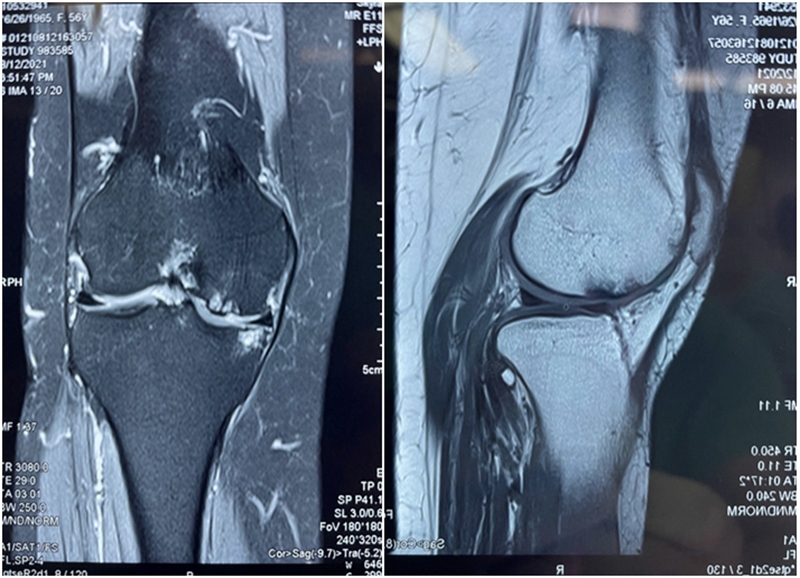

MR显示外侧负重区良好,外侧软骨磨损位于非负重区

术中关节镜证实外侧软骨良好,取出游离体,内侧清理后行胫骨高位截骨术。

内侧软骨负重区II-III级病变

因此,术中用关节镜在髁间窝和髌上囊分别取出了两枚游离体,术中也验证了MR显示的外侧关节面水肿区不是位于外侧间室的负重区,关节镜下外侧软骨为全层软骨,软骨退变区位于股骨滑车沟外侧近潮线处,内侧软骨磨损,部分裸露。故在内侧清理后加做HTO,将力线调整至55%。术者相信这是最利于患者的治疗选择。